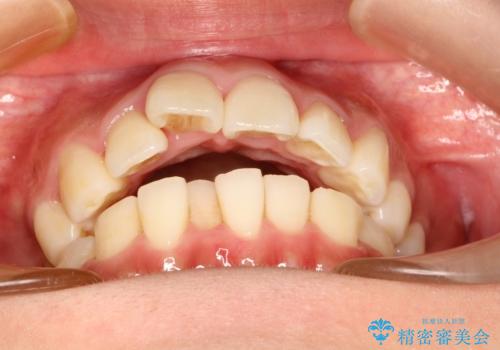

- 上の前歯が出てて、前歯で咬めないとのことで来院されました。

上顎の歯を1本抜歯して、前歯のガタガタと、前方に出ているのを改善する計画としました。